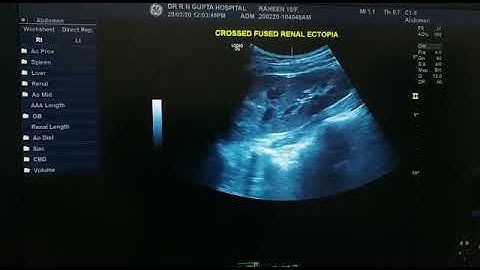

Laparoscopic Pyelolithotomy in Crossed fused Renal ectopia of crossed kidney